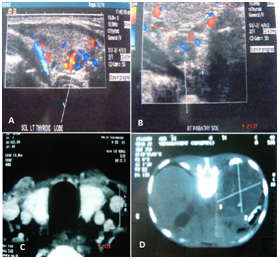

A 20years old male presented with distinct facial appearance, marfanoid habitus, everted eyelids, thick hypertrophied lips, mucosal neuromas and on and off giddiness, sweating and flushing of face. Clinical evaluation revealed sustained hypertension with episodes of superadded paroxysm and thickened corneal nerve on fundoscopic examination. With suspicion of multiple endocrine neoplasia syndrome, ultrasound of neck was performed which revealed bilateral thyroid nodules with enlarged regional neck glands and enlarged parathyroid glands (Figure 2). Contrast enhanced computerized scan of abdomen revealed a large left sided adrenal tumor. His serum calcitonin & serum and urinary catecholamines were raised with marginal elevation of serum calcium. Upper GI endoscopy revealed a vocal cord nodule. A diagnosis of multiple endocrine neoplasia type II B was made based on typical external features together with imaging features of neck and adrenal gland.

Figure 2 A. Doppler USG showing 0.8x0.7 cm ill defined lesion with increased vascularity in the right lobe of thyroid gland. B. Doppler USG showing 0.7x0.5 hypoechoic mass of right parathyroid gland. C. CT scan showing enlarged thyroid gland. D. CT Scan Showing a left adrenal mass.